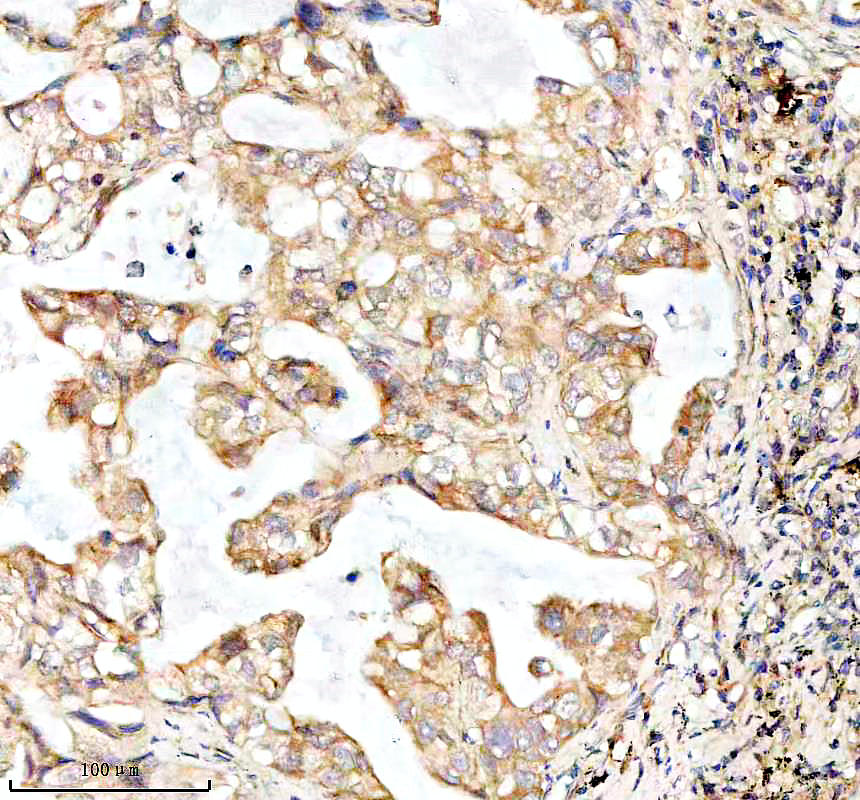

IHC analysis of BNIP3L using anti-BNIP3L antibody (BM5174) .

BNIP3L was detected in a paraffin-embedded section of human rectal cancer tissue. The tissue section was incubated with rabbit anti-BNIP3L Antibody (BM5174) at a dilution of 1:200 and developed using HRP Conjugated Rabbit IgG Super Vision Assay Kit (Catalog # SV0002) with DAB (Catalog # AR1027) as the chromogen.

IHC analysis of BNIP3L using anti-BNIP3L antibody (BM5174) .

BNIP3L was detected in a paraffin-embedded section of human rectal cancer tissue. The tissue section was incubated with rabbit anti-BNIP3L Antibody (BM5174) at a dilution of 1:200 and developed using HRP Conjugated Rabbit IgG Super Vision Assay Kit (Catalog # SV0002) with DAB (Catalog # AR1027) as the chromogen.